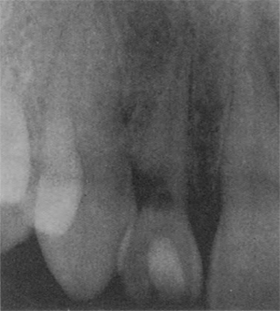

Ա- ներքին ոեզորբցիա: Ախտահարման շրջանում գրեթե բացակայում է արմատախողովակի ուրվագիծը: Բ- ներքին -ռեզորբցիայի բազում օջախներ' ա՛ռաջացած ավտովթարից, 22 տարի անց: Գ-վերին ծնոտի կողմնային կտրիչի աջ կողմի արտաքին վզիկային ոեզորբցիա:

Զգայունության ստուգման արդյունքր դրական է: Արտաքին գրանուլոմայից ճշգրիտ դիֆերենցման համար անհրաժեշտ է կատարել մի քանի ռենտգենո- լոգիական նկարներ' տարբեր պրոյեկցիաներով: Եթե ռենտգեն նկարի վրա լուսավոր հատվածր (ոսկրային հյուսվածքի քայքայված մաս) չի փոխում իր դիրքր, միանշանակ ախտորոշվում է ներքին ռեգորբցիա [1]: